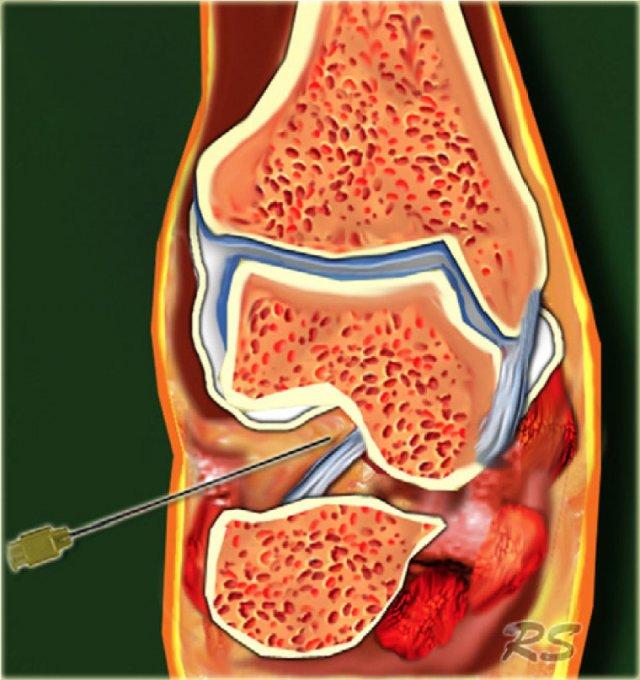

Posterior subtalar joint

Khớp dưới sên hay khớp sên-gót được cấu tạo bởi 3 diện khớp: diện khớp sau rộng đại diện cho bề mặt khớp chính, diện khớp giữa nằm ở phía trong nơi củ chống sên khớp với mỏm trong của xương sên, và diện khớp trước. Chụp khớp dưới sên có thể được thực hiện qua đường tiếp cận trước-ngoài, sau-ngoài hoặc sau-trong. 2-4 ml thuốc cản quang được tiêm vào khớp dưới sên sau.